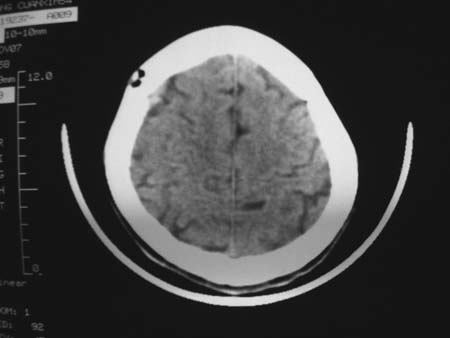

男,54岁,十天前被钢管打伤头顶部,现自述头部不适,视物模糊,并于两天前发觉右枕部有包块,既往未有明显异常.

颅骨多处骨质不完整,内板变薄,右侧额颞部局部呈“穿凿样”骨质缺损,相应区硬膜外密度略增高。多考虑:骨嗜酸性肉芽肿!

颅骨多处骨质不完整,内板变薄,右侧额颞部局部呈“穿凿样”骨质缺损,相应区硬膜外密度略增高。多考虑:骨髓瘤或骨嗜酸性肉芽肿!

颅骨多处骨质不完整,内板变薄,右侧额颞部局部呈“穿凿样”骨质缺损,缺损骨质边缘锐利无硬化,相应区硬膜外密度略增高。多考虑:骨嗜酸性肉芽肿!

颅骨多处骨质不完整,内板变薄,右侧额颞部局部呈“穿凿样”骨质缺损,相应区硬膜外密度略增高。多考虑:骨髓瘤或骨嗜酸性肉芽肿!10天前受伤,不会在2天前才发现头部包块,估计与外伤无关.